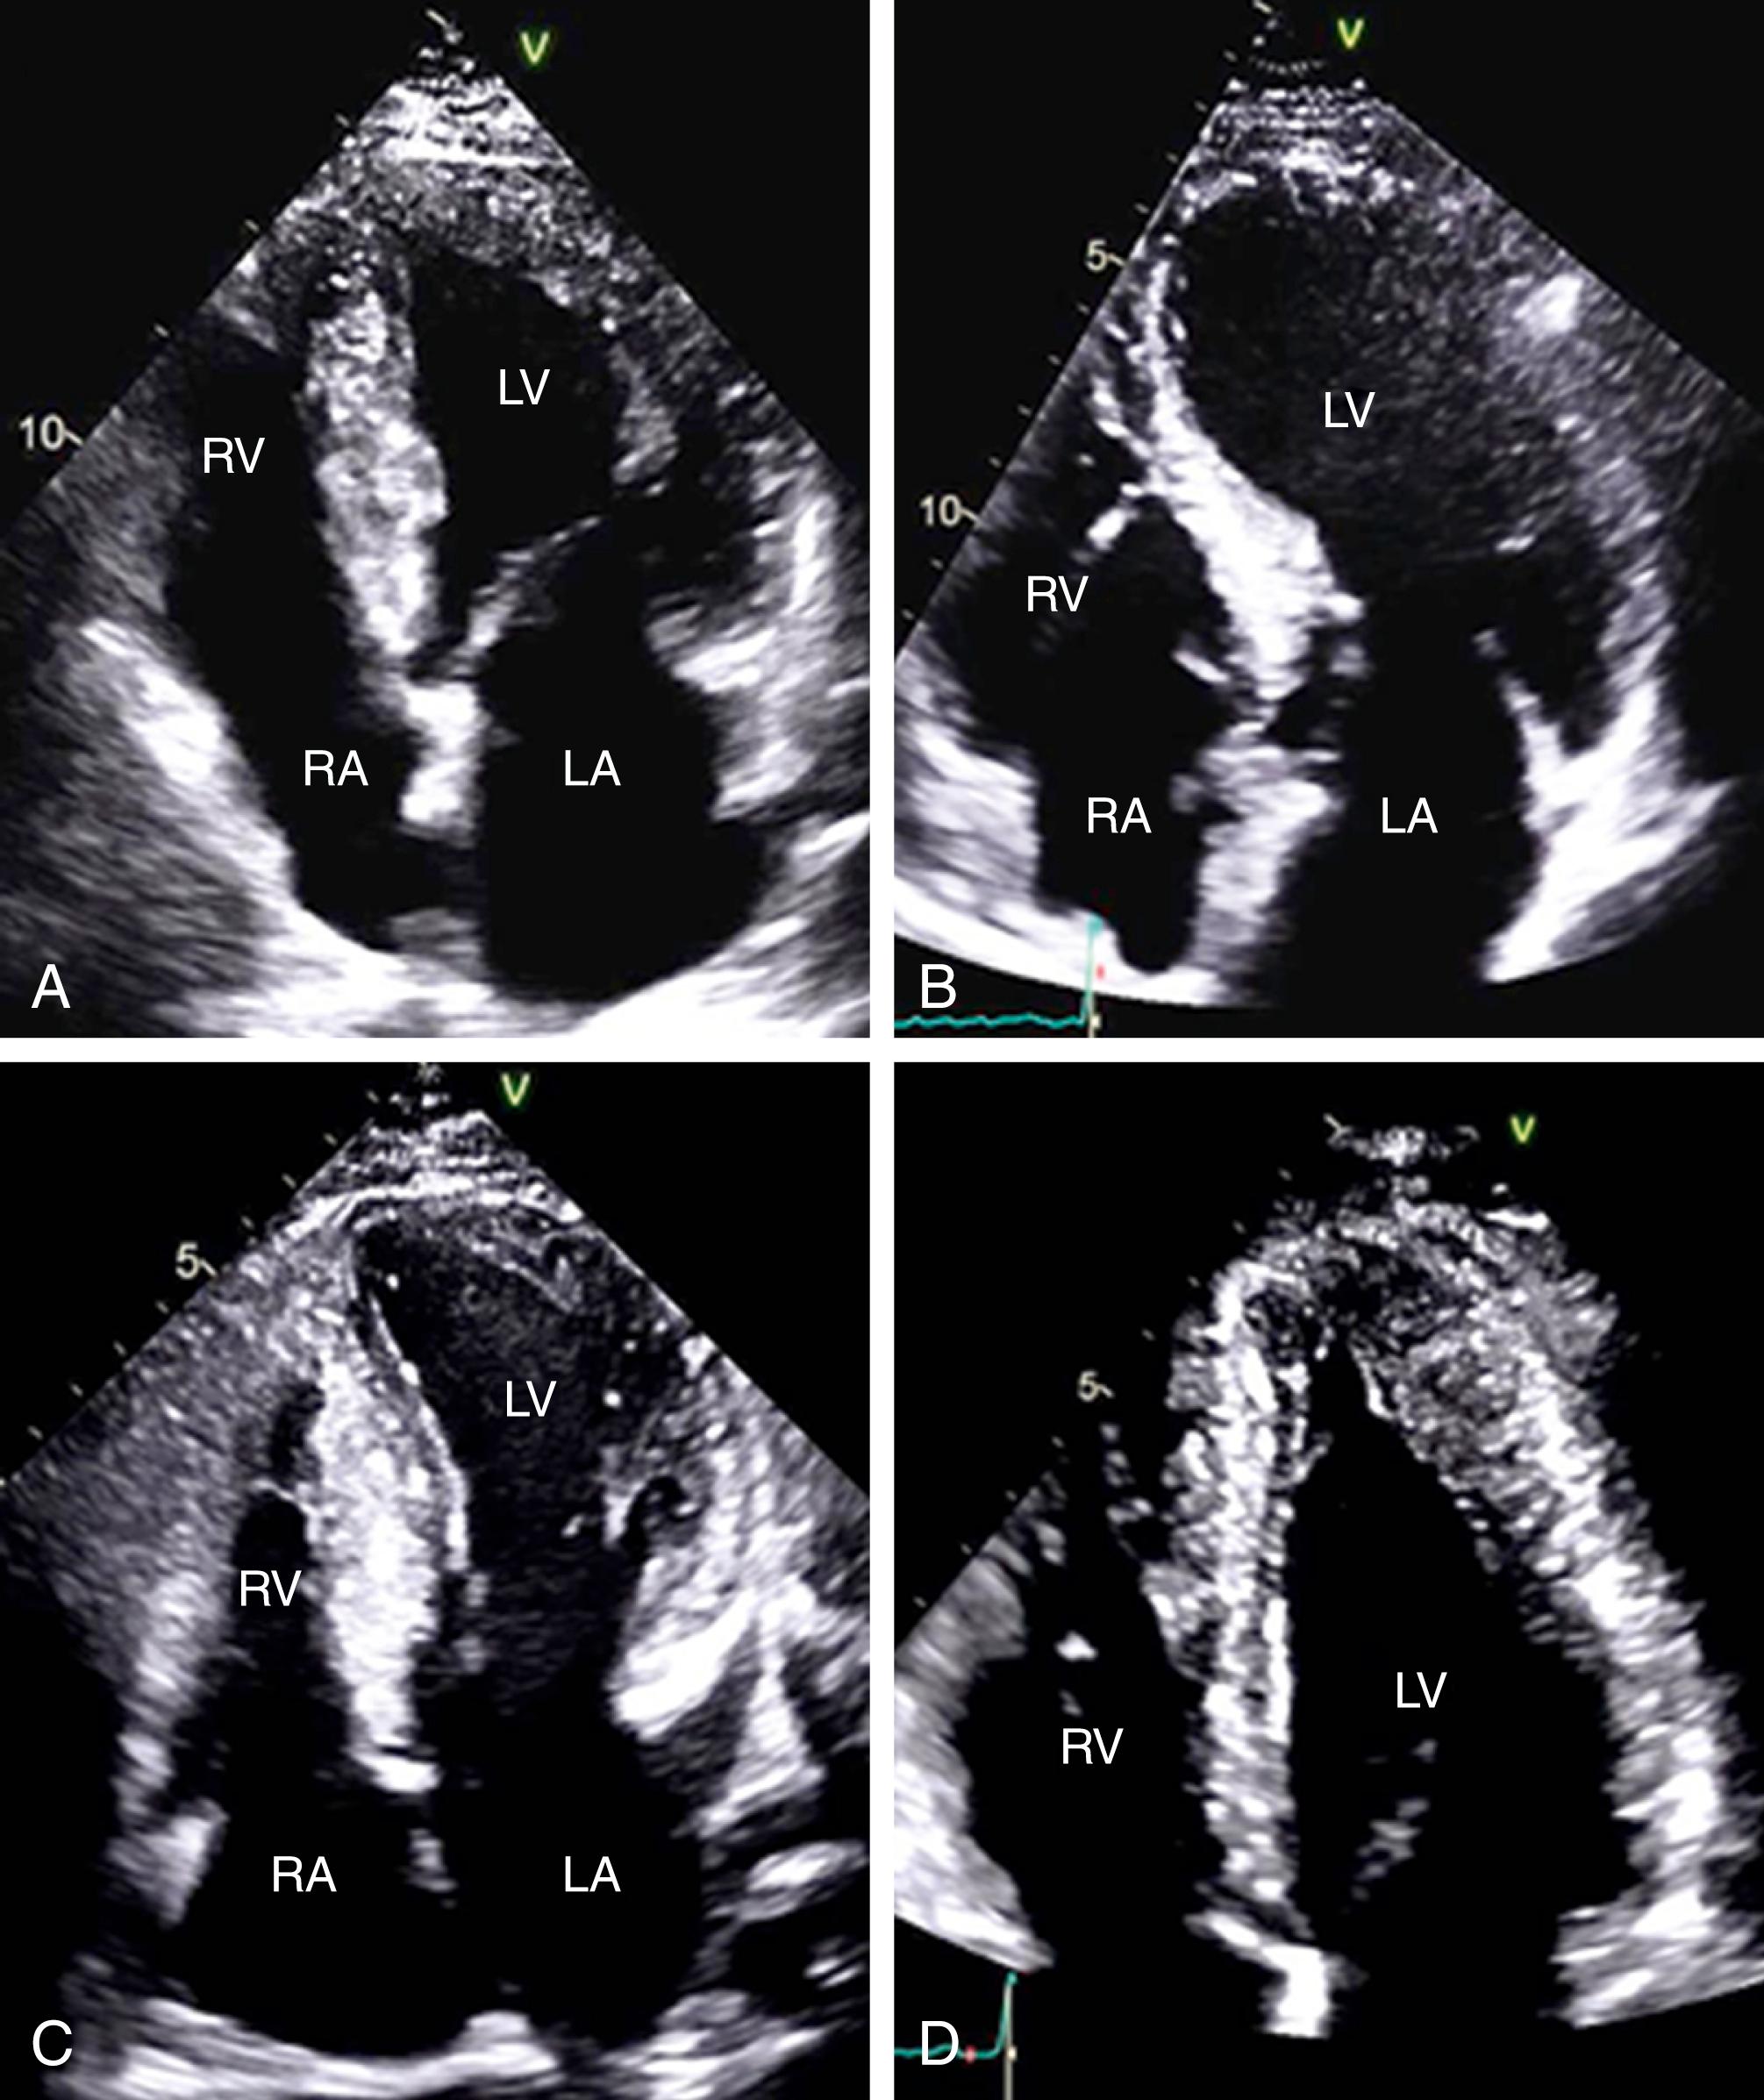

Figure 58.2, Hypertrophic cardiomyopathy morphologies in transthoracic echocardiography. Typical echocardiographic appearances of different hypertrophic cardiomyopathy morphologies including a neutral septum ( A ), a sigmoid septum ( B ), reverse curvature ( C ), and apical hypertrophy ( D ). LA, Left atrium; LV, left ventricle; RA, right atrium; RV, right ventricle.

Figure 58.1, Spectrum of hypertrophic cardiomyopathy morphologies. A, Asymmetric septal hypertrophy with a neutral septum that is neither concave nor convex to the cavity of the left ventricle (LV). B, Sigmoid septum with hypertrophy confined to the basal septum. C, Reverse curvature pattern with a crescentic shape toward the cavity of the LV. D, Apical hypertrophy with hypertrophy confined to the LV apex and normal wall thickness in the basal segments.